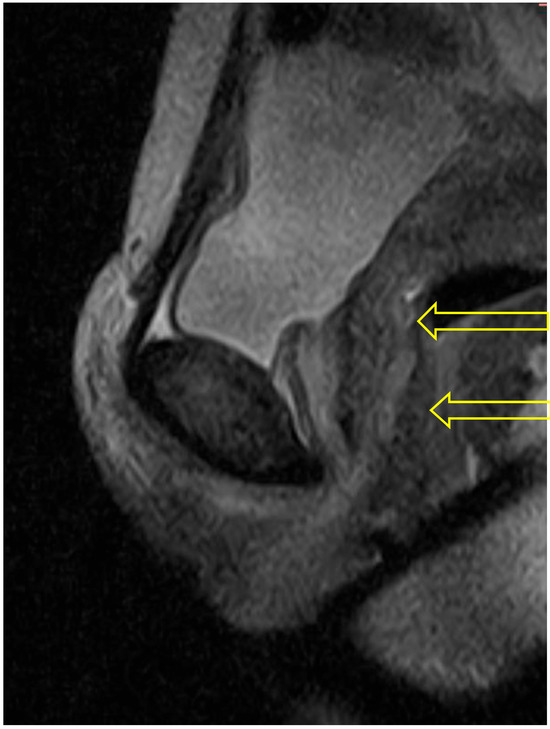

In the supine pose, Savasana, the urethra is seen throughout its length as a circular structure (see Figure 3).

Figure 3. Supine: The 3 scans illustrating this sequence all show the urethra (indicated by arrow) as an uncompressed circular structure at the bladder neck (top), distal urethra (middle), and towards the urethropelvic ligament (bottom).